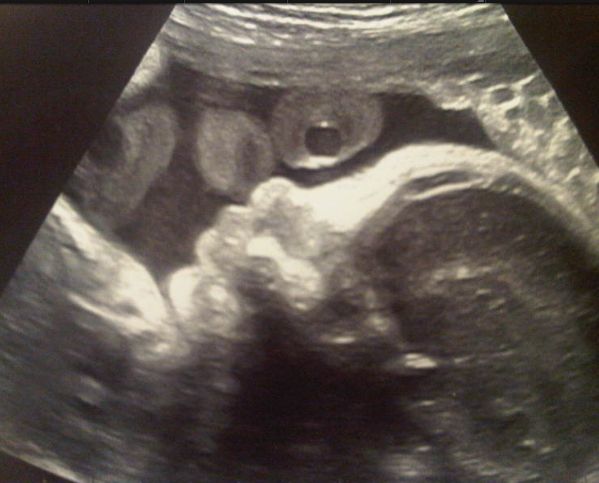

Shakira și iubitul ei, fotbalistul Gerard Pique, au publicat pe Twitter prima fotografie cu copilul lor. Este vorba despre o ecografie 4D în care se pot distinge foarte clar trăsăturile băieţelului care se va naşte la începutul anului viitor.

„Prima lui poză!”, au scris cei doi în explicația imaginii.